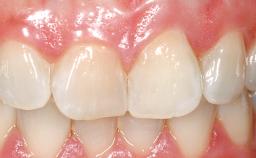

A 42-year-old female patient was referred to our clinic at the School of Dentistry of the University of São Paulo in November 2004, presenting a deficient restoration in the upper left central incisor. The clinical examination revealed no gingival retraction or any signs of gingival inflammation and, therefore, previous periodontal treatment was not considered. The patient presented a high lip line at full smile and a thin tissue biotype. This combination characterized a high-risk situation from an anatomic point of view, which required careful preoperative planning and cautious surgical execution.